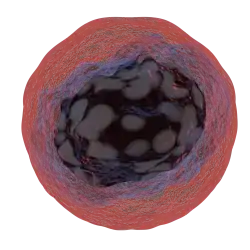

Before going into motivational influencers of cancer screening decisions it is important to have a basic understanding of cancer. Cancer is a complex and diverse disease that comes in many different forms. It occurs when cells within the human body do not undergo apoptosis (programmed cell death) and continue to grow. These cells then create a mass which is commonly referred to as a tumour. Unfortunately cancer is not a new disease, there has been mentions of cancer from as early as 3000 BC. In 2018, the International Agency of Research on Cancer reported over 233, 773 individuals within Australia and New Zealand, 3, 679, 584 individuals in America, and 4, 229, 662 in Europe living with cancer.Regrettably, at this current time there is no hard and fast cure for cancer. However, this does not mean it is not treatable. There are many forms of treatments available that have varying rates of success depending on the development and location of the cancer. The three most common include Chemotherapy (the removal of cancer cells using anti-cancer drugs), Radiation therapy (the use of x-rays to damage or destroy cancer cells) and Surgery. Other less common treatments include; Complementary therapy, Hormone therapy, Immunotherapy and Palliative care. To this day as our knowledge and understanding of cancer grows so do our treatment methods. If these treatments pass through all the legal and ethical boards then they to what is known as clinical trials. These trials allow researchers to test the effectiveness of the treatment.Due to the lack of cure, one of the most crucial techniques to decreasing mortality rates of cancer, is early detection! The later the cancer is detected the harder it is to treat as the mass typically is bigger and spread out across the body. Two of the major components of early detection are education and cancer screening. Though educational events and programs provided by general public health organizations, such as the World Health Organisation (WHO), people are provided with the necessary knowledge that they would need to identify cancer symptoms early. This allows them to be proactive and seek out assistance if they believe that they are experiencing any potential symptoms. Education also brings awareness to proactive health actions that are available to the general public. Which lead to the second key component of early detection, cancer screening. Cancer screening is a specific but simple test that allows for the early detection of any cancerous cells or potential future risks. Regrettably, as cancer is such a multifarious disease, at this current time there is no universal test. However, there are screening options for various specific types of cancer including but not limited to: breast cancer, bowel cancer, and colorectal cancer. Despite the increase in screening options available to the general public, the percentage of those undergoing a screening test remains low.